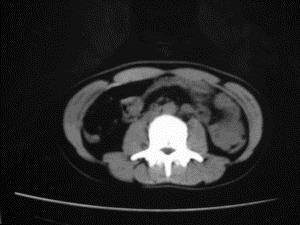

患者女,20岁,被车撞伤3小时,pe:全腹肌紧张,压痛反跳痛,以右上腹为著,肠鸣音减弱。有手术结果。![]() ![]() ![]() ![]() ![]() ![]() ![]() ![]() ![]() ![]() ![]() ![]() ![]() ![]() ![]() ![]() ![]() ![]() ![]() ![]() ![]() jiajie发言: ![]() 考虑空腔脏器穿孔。 dyqct发言:考虑:1、肝左叶外侧段断裂伤伴少量腹血。2、空腔脏器穿孔。 fangzheng发言:仅见腹腔内游离气体,提示空腔脏器穿孔。 guoke发言:胃内密度增高,肠腔内充满气体,考虑肠腔破裂出血 mmg94发言:胃后壁见一增厚软组织密度影,肝左叶前见游离气体影,左腹腔内局部肠管壁、系膜增厚。并见类圆形软组织。以上征象提示消化道管腔破裂,小肠、肠系膜挫裂伤,腹腔血肿形成。 拾荒者发言:肝实质密度不均匀,胃内见不均匀高密度影。考虑:肝挫裂伤,胃内应激性溃疡出血。 守望可可西里发言: 以下是引用jiajie在2006-6-20 15:49:00的发言:[br] [br][br]考虑空腔脏器穿孔。jiajie老师,我鼓起了很大的勇气才决定给您唱个反调儿,如果我错了,请您一定给我指出来,谢谢您了。我反复看了解剖图谱,觉得您所说的“考虑空腔脏器穿孔”上图所用箭头标明的不是游离气体。请您看以下几幅图片: ![]() ![]() ![]() ![]() ![]() ![]() ![]() ![]() 再请您看向医生老师发表的解剖图谱3幅 ![]() ![]() ![]() 这以下几幅图,我认为是肝包膜下积血。不过,说实在话,我没有发现有明显的肝挫裂伤。不对的地方请您一定指出来,再次感谢您了,jiajie 老师! ![]() ![]() ![]() ![]() 这下面几幅图片,我认为有明显的左中上腹部小肠损伤。 ![]() ![]() ![]() ![]() ![]() ![]() ![]() ![]() jiajie 老师,估计我说的是错误的,但我实在闹不明白,请您一定不要笑话我,并指出我的错误,以便于我减少工作中的失误。再次感谢您了,jiajie 老师! 至于胃内的不均匀高密度,我认为拾荒者战友说的有道理,胃内应激性溃疡出血和胃内容物混合所致。 手术结果:左肝叶(iv段)前缘长约8cm挫裂伤口,舌叶根部下< |